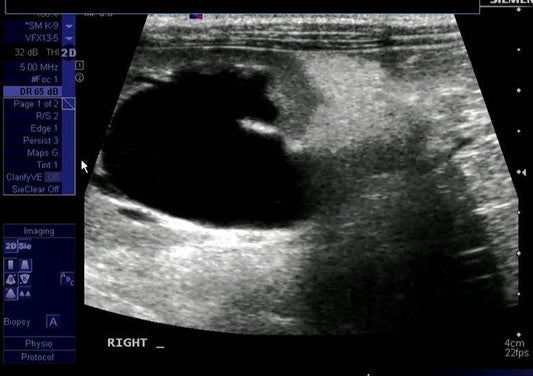

Collection: Ultrason